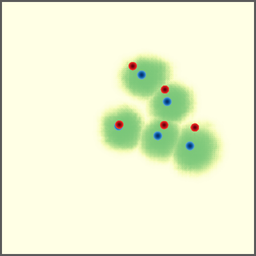

Shift-Invariant Tracking. The POINT network benefits from the shift invariant property of the convolution operation, which makes it less sensitive to the in-plane offset of the DRRs. Figure 8 shows some tracking results from the POINT network. Here the odd rows show the (a) X-ray and (b-d) DRR images. The heatmap below each DRR shows the tracking result between this DRR and the leftmost X-ray image. The red and the blue marks on the X-ray and DRR images denote the POIs. The red and the blue marks on the heatmaps are the ground truth POIs and the tracked POIs, respectively. The green blobs are the heatmap responses and they are used to generate the tracked POIs (blue) according to Equation (7). The numbers under each DRR denote the mPD scores before and after the tracking. As we can observe that the tracking results are consistently good, no matter how much initial offset there is between the DRR and the X-ray image. This shows that our POINT network indeed benefits from the POI convolution layer and provide more consistent outputs regardless of the in-plane offsets.

Refer to caption

(a)

(b) 13.6 \rightarrow 7.3

(c) 22.9 \rightarrow 9.0

(d) 37.1 \rightarrow 7.8

(e)

(f) 19.5 \rightarrow 8.7

(g) 26.0 \rightarrow 9.5

(h) 41.1 \rightarrow 11.4

(b)

(c)

(d)

Figure 8: POI tracking results. (a) X-ray image. (b-d) DRR images with different in-plane offsets. The heatmaps of the tracking results are all aligned with the X-ray images and appear similar, showing the shift-invariant property.